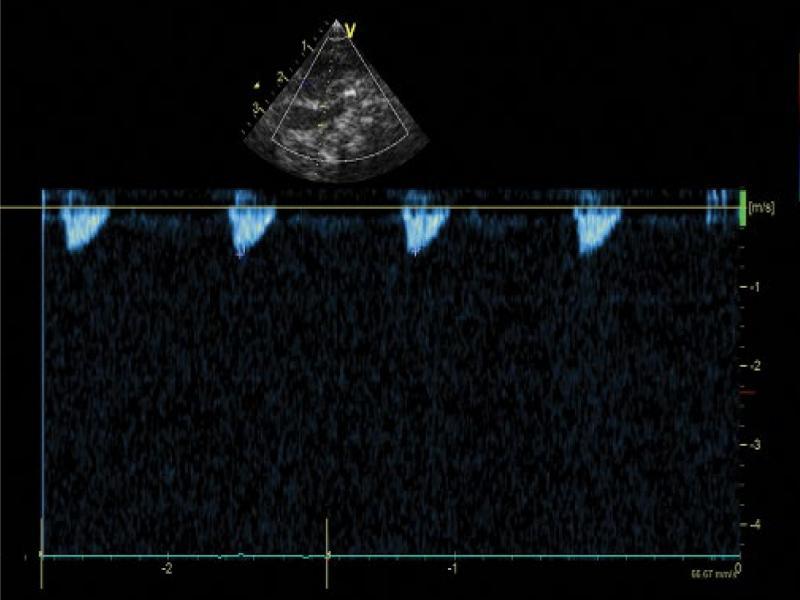

We attempted to experimentally clamp the posterior descending artery (PDA) during echocardiography-guided cardiac correction and found no deficit in blood supply in the left upper limb. PDA was ligated and divided. A total correction of tetralogy of Fallot was performed. The post-operative period was uneventful. Postoperative ultrasonography still showed reversed flow in the left vertebral artery (LVA), representing the only supply of the left subclavian artery (LSA) (Fig. 10 and Fig. 11 show altered flow in the left common carotid artery and left vertebral artery after defect correction and ductus arteriosus closure). The flow in both arteries was systolic and high-resistance, which confirmed the decreased volume of cerebral steal. It may be therefore concluded that the closure of ductus arteriosus reduced the risk of cerebral perfusion deficit, with maintained blood supply to the left upper extremity.

Recorded flow in the left vertebral artery using pulse Doppler. Systolic flow. Closure of the ductus arteriosus undoubtedly reduced cerebral steal with maintained perfusion in the left upper extremity